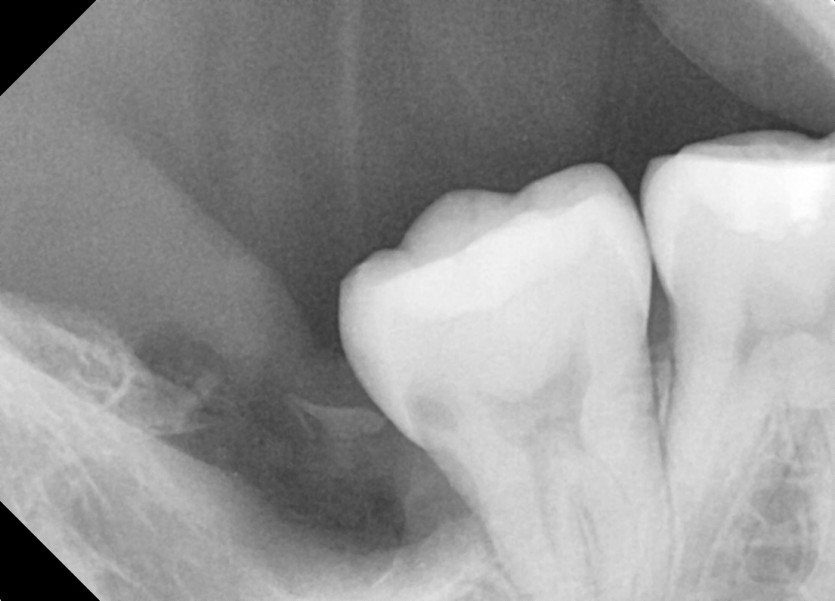

#48 사랑니 발치

구강 외과 전문의가 당일 발치했습니다.